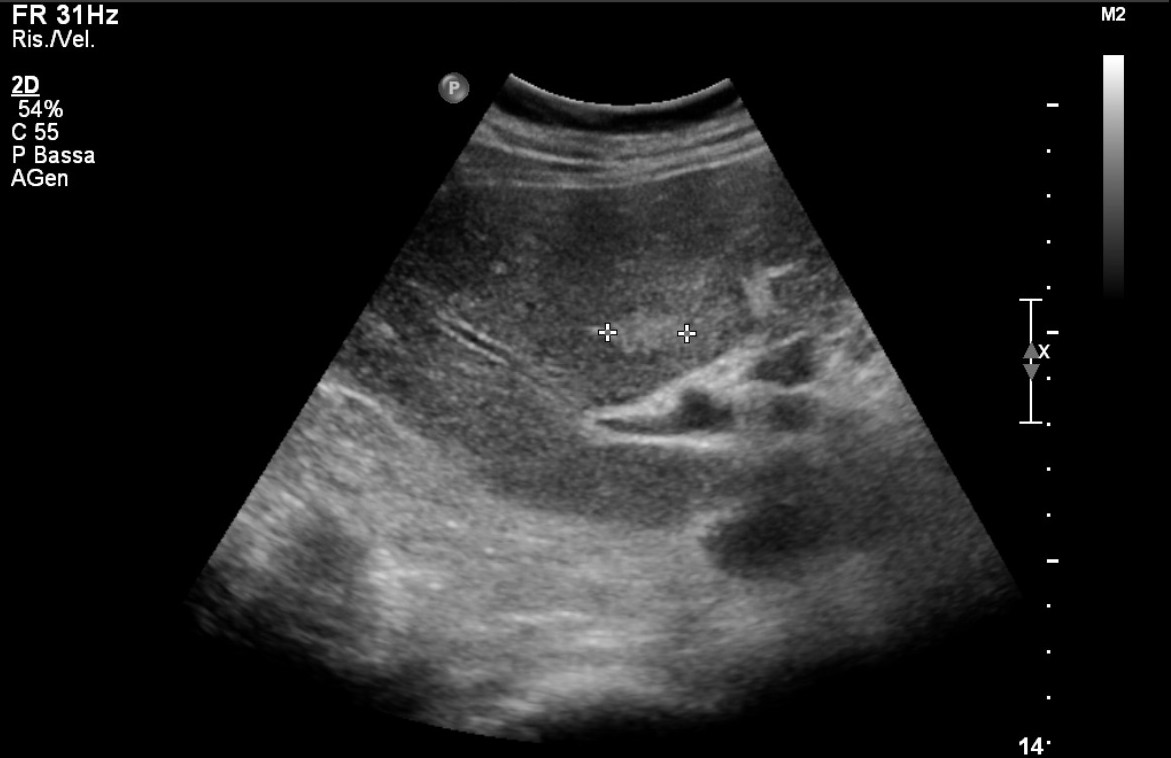

Ad oggi sono state identificate con l’ecografia addominale prevista dal protocollo, 9 neoplasie del parenchima epatico: 5 angiosarcomi (Fig. 1-4) (di cui 2 viventi) e 4 epatocarcinomi (Fig. 5-7) (di cui 1 vivente), successivamente sottoposte a studio TC e tutte confermate dalla diagnosi istologica.

Fig.3. Caso 2 di angiosarcoma epatico

Fig.4. Caso 2 di angiosarcoma epatico